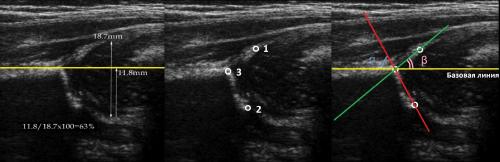

На первом этапе тазобедренный сустав сканируют в продольной плоскости. Проводят основные линии, измеряют костное покрытие головки, расстояние от лобковой кости до головки, ∠α и ∠β, а также определяют тип строения по Графу.

Датчик располагают в проекции большого вертела параллельно поясничному отделу позвоночника. Найдите самое глубокое место вертлужной впадины. Отрегулируйте наклон датчика, чтобы линия тела подвздошной кости лежала строго горизонтально (2).

Пока головка бедренной кости хрящевой плотности, имеется акустическое окно для исследования вертлужной впадины. При продольном сканировании документируют по два снимка: первый — обзорный, второй — с линиями и углами.

Проведите базовую линию по наружному контуру подвздошной кости и обозначьте головку бедренной кости, аппарат автоматически вычисляет степень костного покрытия головки. Костное покрытие головки в случаях предвывиха 40-50%, подвывиха

Когда головка смещается кнаружи, освободившееся пространство заполняет гиперэхогенная круглая связка и жир. При подвывихе и вывихе расстояние от лобковой кости до головки >6 мм, разница между бедрами >1,5 мм (3). Толстый хрящ лобковой кости считают вариантом нормы (4).

Линии костной (красная) и хрящевой (зеленая) крыши проходят через костный выступ, а так же начало Y-хряща и центр гиперэхогенного кончика суставной губы, соответственно. Степень развития костной крыши определяет ∠α, а хрящевой крыши ∠β.

Если край подвздошной кости округлый, костный выступ определяют в точке перехода дуги наружного контура вертлужной впадины в дугу наружного контура подвздошной кости. Обратите внимание, все линии проходят по наружному контуру костей.